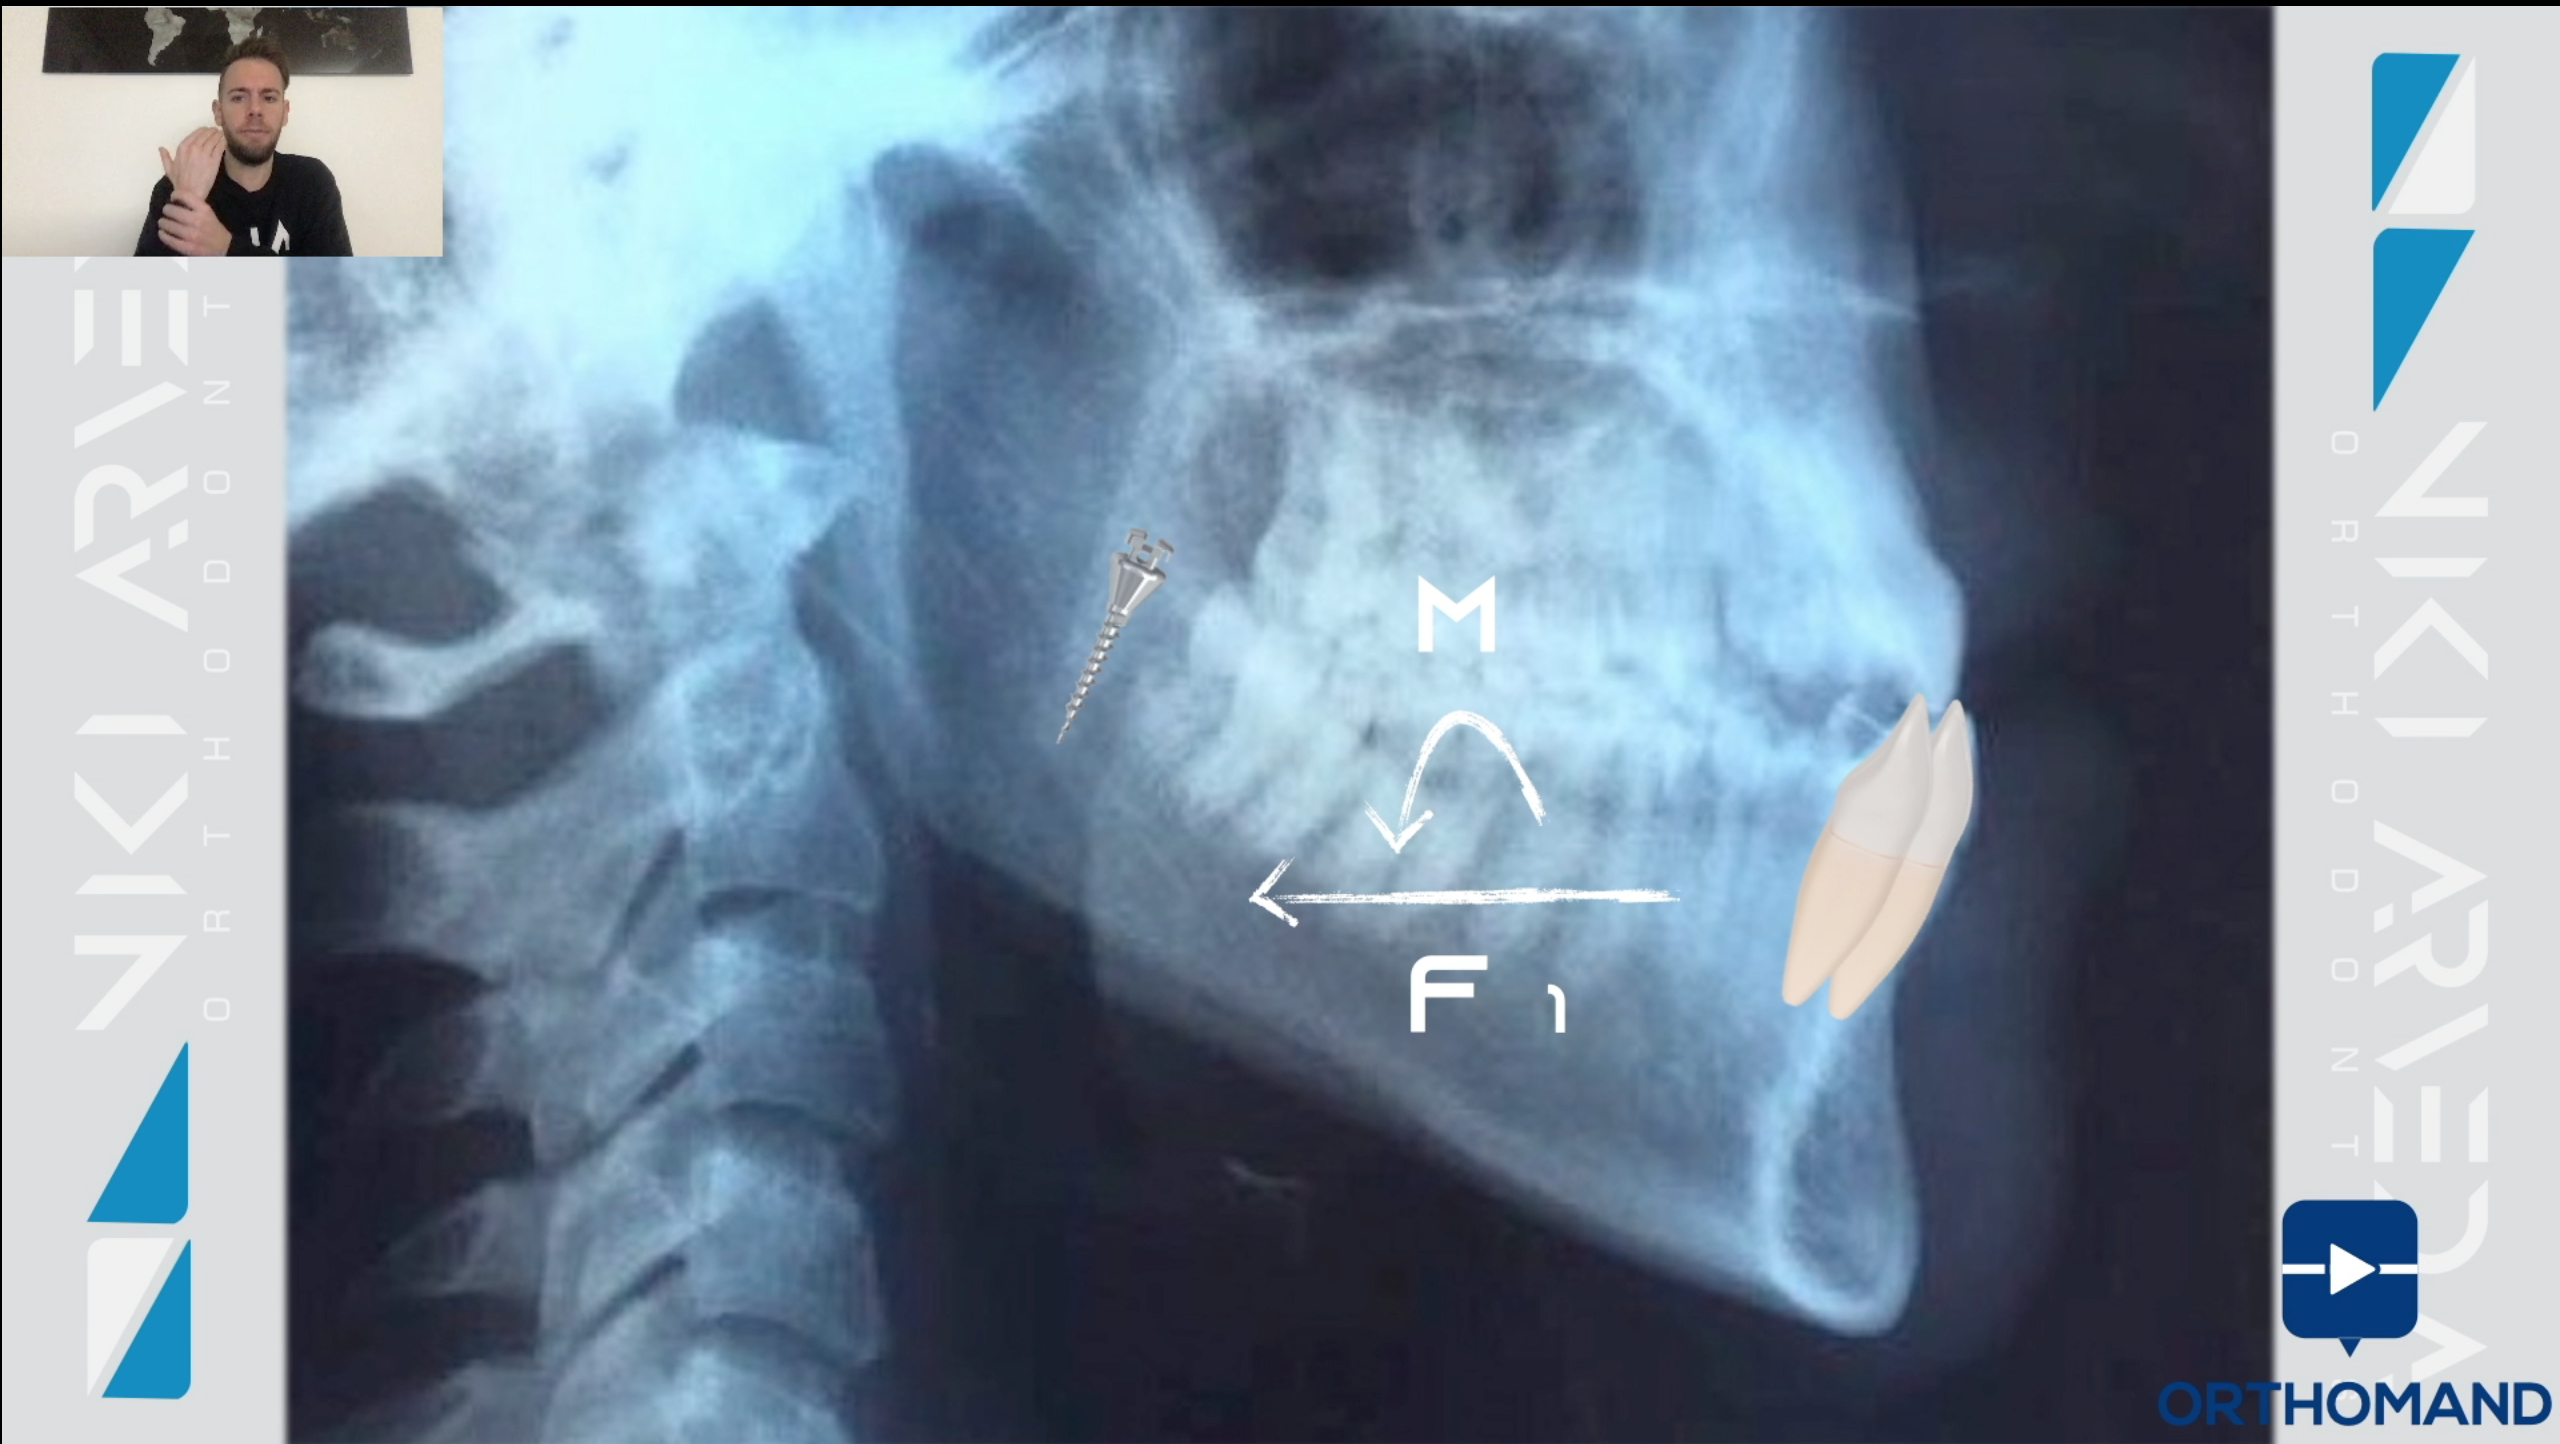

- Strategie terapeutiche per ottenere un buon camouflage: estrazioni, elastici di classe e ancoraggio scheletrico

- Biomeccanica della distalizzazione dell’arcata inferiore

- Ruolo della divergenza scheletrica nei camouflage delle 3° classi